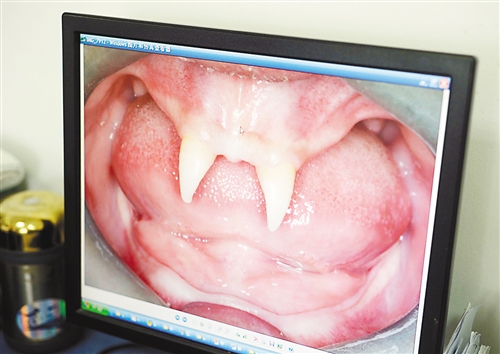

12月18日,16歲的張成(化名)從小到大,只有上顎部分有兩顆牙,看上去更像長著一對獠牙。 記者熊明攝

張成是貴州銅仁地區(qū)思南縣人,從生下來就似乎得了一種怪病,身上毛發(fā)稀少,面部發(fā)育也不好。更奇怪的是,別人家的孩子都長牙吃東西了,他卻一直長不出牙齒,最后只在上顎部分冒出兩顆比較突出且對稱的牙齒,看起來就像一對獠牙。

在母親陪同下,張成來到西南醫(yī)院口腔頜面外科就診。經(jīng)醫(yī)生檢查,張成被確診為無汗型外胚層發(fā)育不良。

據(jù)介紹,該病的發(fā)病率不到十萬分之一,是一種較為罕見和嚴重的基因病,多見于男性。如果患上這種病,其乳牙或恒牙會先天性缺失,還可能伴隨淚腺發(fā)育障礙、視光敏感、視力下降、聽力障礙、唇腭裂、發(fā)音困難、身材矮小、乳房發(fā)育不良等癥狀。以西南醫(yī)院為例,每年都會遇見一兩例這樣的患者,但像張成這樣嚴重的,非常少見。